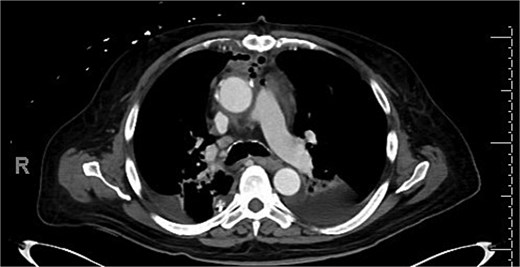

Intravenous (IV) daptomycin and meropenem were continued postoperatively per recommendation of our institution’s infectious disease team and notably this regimen did not cover S. maltophilia. On post-operative day 10, the patient had increasing leukocytosis and increased pressor requirements. Computerized tomography (CT) scan was performed that was concerning for mediastinitis (Fig. 1). Blood cultures and pleural fluid cultures from the remaining chest tubes were sent, which eventually grew out S. maltophilia. The patient was taken back to the operating room on post-operative day 10. The mediastinum was washed out and the chest was left open again using NPWT. Cultures from the OR also grew out S. maltophilia. Two days later (on post-operative day 12), the patient again underwent mediastinal washout and an omental flap (Fig. 2) was mobilized laparoscopically and placed in the mediastinum. The mediastinum was washed out with sodium hypochlorite (0.4%–0.5%) and boric acid (4%) diluted in water, and tobramycin beads were left in the mediastinum. The sternum was closed with wires and the soft tissue was closed with absorbable suture. The skin was closed with staples. The patient was discharged on post-operative day 35 from his transplant with IV daptomycin and IV bactrim for an additional week to finish a 4-week course. He has followed up multiple times in the clinic since his discharge. At present, he is 4 months out from his transplant without any signs of infection and has been off IV antibiotics but remains on Bactrim SS PO daily for prophylaxis, which does provide some coverage of S. maltophilia.